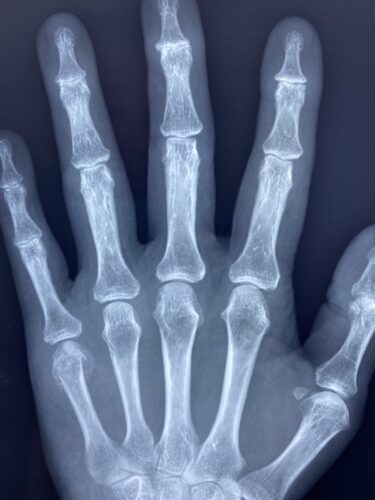

第16回整骨研究会「賜恩」研修会開催

さわやか千葉県民プラザ(指骨骨折)

第18回整骨研究会「賜恩」研修会開催